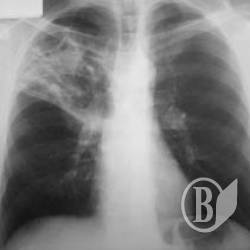

Найбільш розповсюдженими у 2012 році були хвороби органів дихання.

Захворюваність на них становила 33,3 тис. випадків на 100 тис. населення.

А також травми, отруєння та деякі інші наслідки дії зовнішніх причин – 5,4 тис.; хвороби системи кровообігу – 4,5 тис.; шкіри та підшкірної клітковини – 4,1 тис.; сечостатевої системи, ока та його придаткового апарату – 3,6 тис. випадків по кожному класу захворювань; кістково-м’язової системи та сполучної тканини – 3,4 тис.